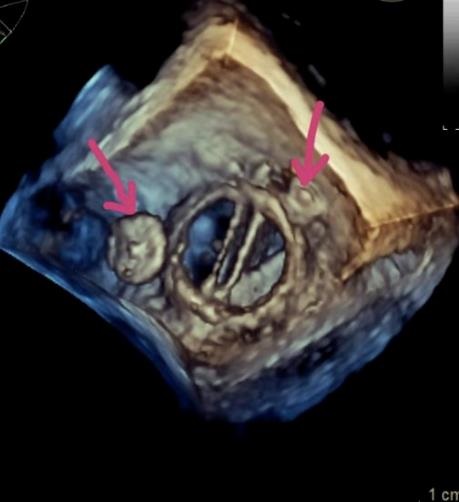

(术中三维超声显示两处瓣周漏完美封堵)

两项技术的融合及术者高超的技巧,避开重重障碍,泥鳅导丝像长了眼睛一样精准通过了瓣周漏,并成功送入输送长鞘,分别将2枚封堵器在瓣周漏处完美释放。

术中食道超声显示封堵器位置良好,两处瓣周漏血流完全消失,二尖瓣功能正常,手术顺利完成,整个过程不到2小时,术后患者直接回病房,目前恢复良好,将于近日出院。